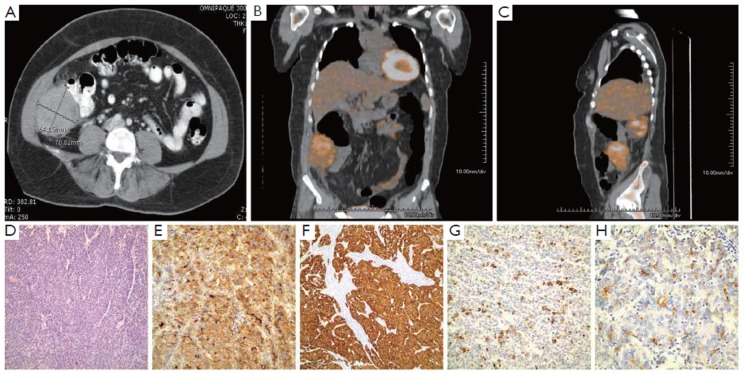

The patient is a 44-year-old female who presented at the age of 42 years in April 2008 with right lower quadrant pain, gradually increasing over a few months prior to evaluation. Work up included a CT scan of the abdomen and pelvis, which revealed a 6.4 cm × 7.0 cm heterogeneous mass in the right lower quadrant (RLQ) interposed between the right lateral abdominal wall and the wall of the ascending colon (Figure 1A). The colon itself and the liver appeared unremarkable, and minimal free fluid in the cul-de-sac was noted. A CT guided biopsy of the mass showed a moderately differentiated adenocarcinoma of unknown origin. She underwent an extensive gynecologic work up, colonoscopy and upper endoscopy, all of which were negative. The patient was taken for an exploratory laparotomy in June 2008 that showed a 7 cm well-encapsulated heterogenous tumor in the right paracolic gutter invading into the retroperitoneum and involving the abdominal wall. The liver and the gallbladder appeared normal with the exception of a 1.5 cm × 1.0 cm calcified lymph node seen on the undersurface of the liver, at the base of the gallbladder. This was removed and pathology showed non-small cell carcinoma with hepatoid features. Intraoperative gynecologic and urologic consults were done, which ruled out involvement of these organ systems.

Figure 1.

A: CT scan of the abdomen showing the RLQ mass; B: The RLQ mass is PET-avid; C: Lateral view of the PET-avid RLQ mass; D: Hepatoid pattern; E: Diffuse 3+ AFP; F: Diffuse 3+ CAM; G: Patchy 3+ HepPar; H: Canalicular CEA staining.

She subsequently underwent a PET scan in July 2008, which revealed mild uptake in the mass, and no metastatic lesions (Figure 1B, C). The patient still had significant right lower quadrant discomfort, anorexia and weight loss. Decision was made to go ahead with surgical resection of the RLQ mass, mostly to obtain more pathologic information, but also to provide some therapeutic benefit. Pre-operative blood work revealed a high alpha-fetoprotein (AFP) of 62,409 ng/mL and normal CEA of 0.8 ng/mL, CA-125 of 19 U/mL, CA 19-9 of 8 and β-HCG less than 5 mIU/mL. In August 2008, she underwent repeat laparotomy exposing the tumor that extended into the right abdominal wall. It appeared to be intimately attached to the ascending colon and the cecum although not directly invading the colon. A right hemicolectomy was done and the posterior extension of the mass was identified. It did not involve the ureter or the kidney, and the mass was dissected off the retroperitoneum. Pathology showed a 7.5 cm high-grade adenocarcinoma with hepatoid differentiation. Additional smaller satellite foci were identified microscopically. The tumor was composed of medium-sized polygonal cells with granular eosinophilic cytoplasm and frequent mitosis, arranged in a trabecular pattern resembling hepatocellular carcinoma type (hepatoid) morphology (Figure 1D). The right colon showed some adhesions on the serosal surface but no evidence of tumor. The appendix was negative for tumor. The tumor invaded the posterior fibroadipose tissue but the excised skeletal muscle was negative. The morphological differential diagnosis included metastatic hepatocellular carcinoma, hepatoid adenocarcinoma or hepatoid germ cell tumor. Immunohistochemical stains were performed and showed diffuse 3+ AFP staining (Figure 1E), diffuse 3+ CAM 5.2 staining (Figure 1F), patchy 3+ HepPar staining (Figure 1G) and luminal/focal canalicular polyclonal CEA staining (Figure 1H) along with positive CK20 and CK7. Germ cell markers CD30, OCT 3/4 and PLAP (Placental alkaline phosphate) were negative. Ten mesenteric lymph nodes were negative for cancer. The gallbladder fossa nodule showed similar histopathological features.